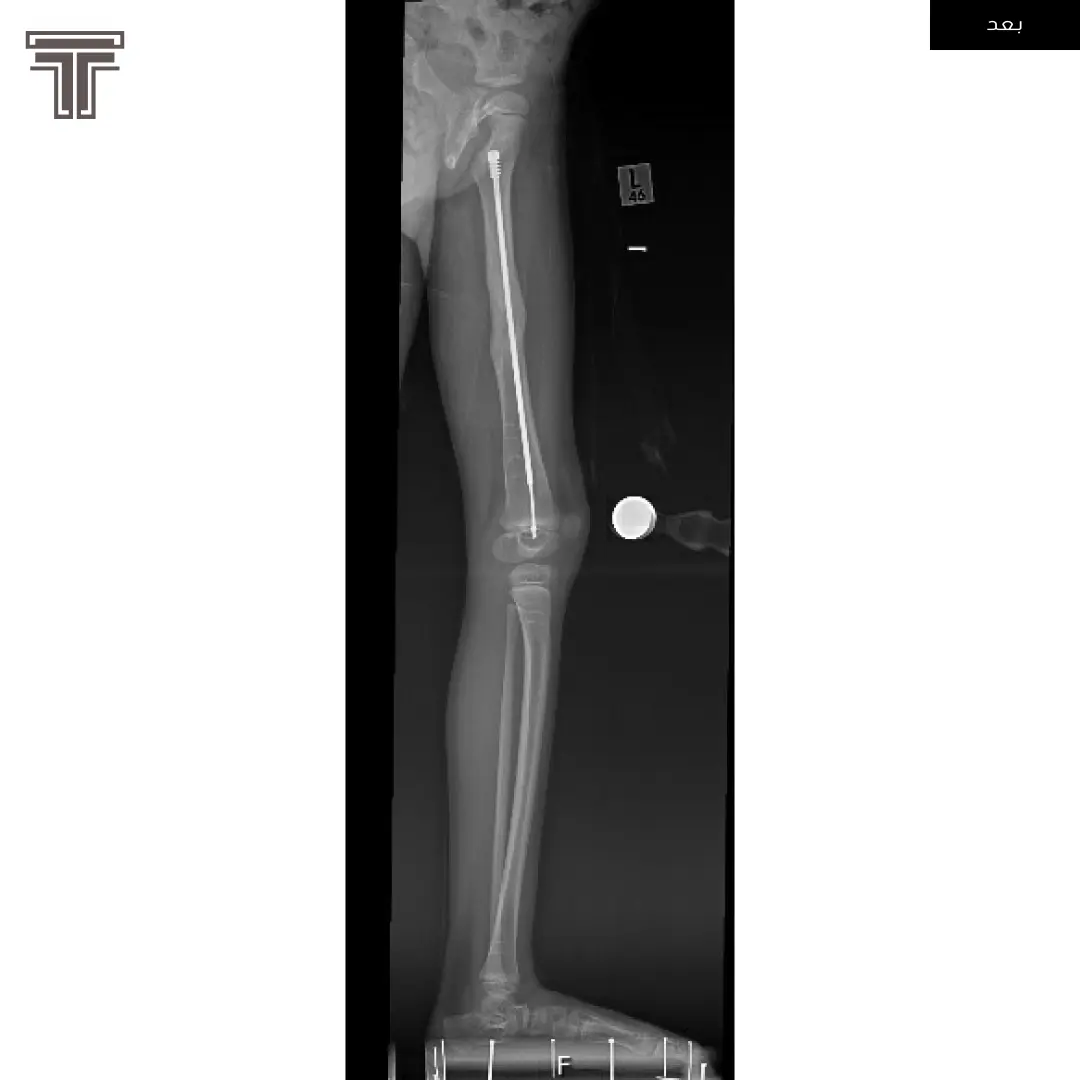

عندما تهمل خلوع الورك الولادية لعمر كبير يصبح علاجها وارجاعها صعب ويتطلب عملية استبدال للمفصل. وفي مثل هذه العمليات وتحديدا في استبدال مفاصل خلوع الورك الولادية يتطلب تقصير في طول الفخذ لتجنب المضاعفات.